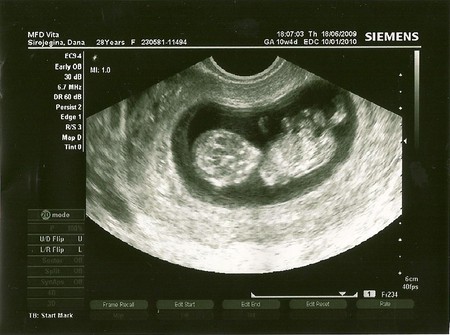

11-ая неделя...узи ;-)

Сегодня была на приёми,делали узи со всеми замера.по научному наверное называется скрининг.У нас всё в норме,малыш догнал по размерам свой акушерский срок-10 недель и 5 дней.После всех замеров , медсестра позвала Полинку в кабинет,посмотреть на малыша.Мой старший ребёнок был в шоке)))))особенно от того,что когда она подошла к монитору,мой младший ребёнок,повернулся к ней и помохал ручкой))))Поля до сих пор не может успокоиться-МАМА МАЛЫШ МЕНЯ УВИДЕЛ И ПОМАХАЛ!!!!!

И не говори,я как бы уже типо опытная)))но вчера опять была в шоке....только три недельки назад,там был малышок похож на большое зёрнышко боба))))а вчера....руки ноги,всё в движение,мозг такой красивый))))медсетра сказала-футболист))))я сказала-учёный))))а Полинка молча стояла и не моргала)))))

Девочки,я тоже думала.вернее была уверенна,что будут по живуту,ан нет,делали вагинальное!!!!Врач просто изначально,до узи сомневалась,будут ли делать сегодня замеры,просто 3 недели назад,малышонок был ещё маловат и немного отстовал от срока.А в этот раз он догнал))))и можно было всё замерить и написать в карту.Я думаю,что это не панацея, и многим делают узи на таком сроке по животу.НО мне вчера делали вагинальное,обосновываея это тем,что так лучше видно на моём сроке!